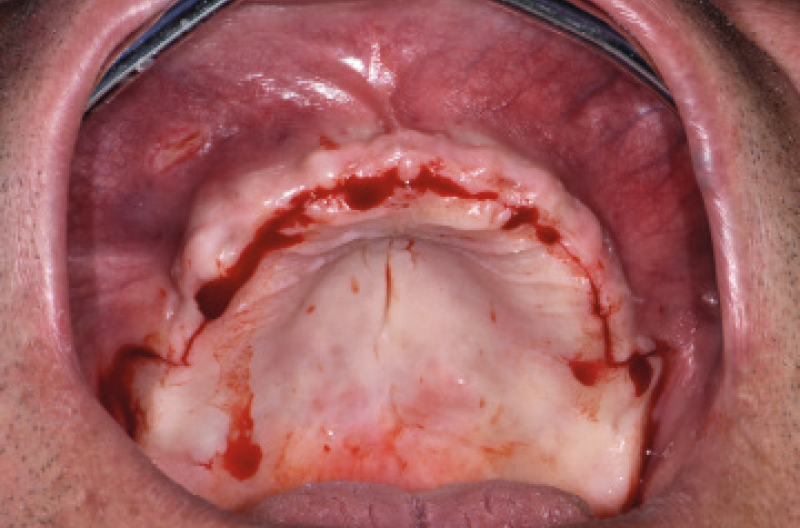

Ho riaperto il mascellare superiore con un lembo a spessore parziale palatino e con scarichi solo distali per limitare al minimo il trauma allŌĆÖosso perimplantare; dopodich├® ho scelto i monconi MUA pi├╣ idonei, tutti GH 1,5 mm uno diritto, tre angolati a 15┬░ e due angolati a 25┬░. Una volta parallelizzati, ho attivato i monconi MUA negli impianti e avvitato gli adattori Conic per trasformarli in monconi MUA-Conic. Dopo aver suturato il lembo, ho attivato le cappette Fixed sui monconi MUA-Conic e poi si ├© proceduto alla ribasatura della protesi opportunamente scaricata in corrispondenza dei monconi MUA-Conic. Durante la procedura intraorale di inglobamento delle cappette Fixed, la protesi si ├© autocentrata in occlusione con la protesi conometrica fissa provvisoria inferiore. Infine la protesi ├© stata rifinita, riposizionata in bocca e attivata (Figg. 30-37). A distanza di un mese entrambe le Toronto provvisorie sono state rimosse e ribasate per un migliore condizionamento del tessuto gengivale (Fig. 38).

Fig. 30 – Riapertura del superiore con lembo a spessore parziale